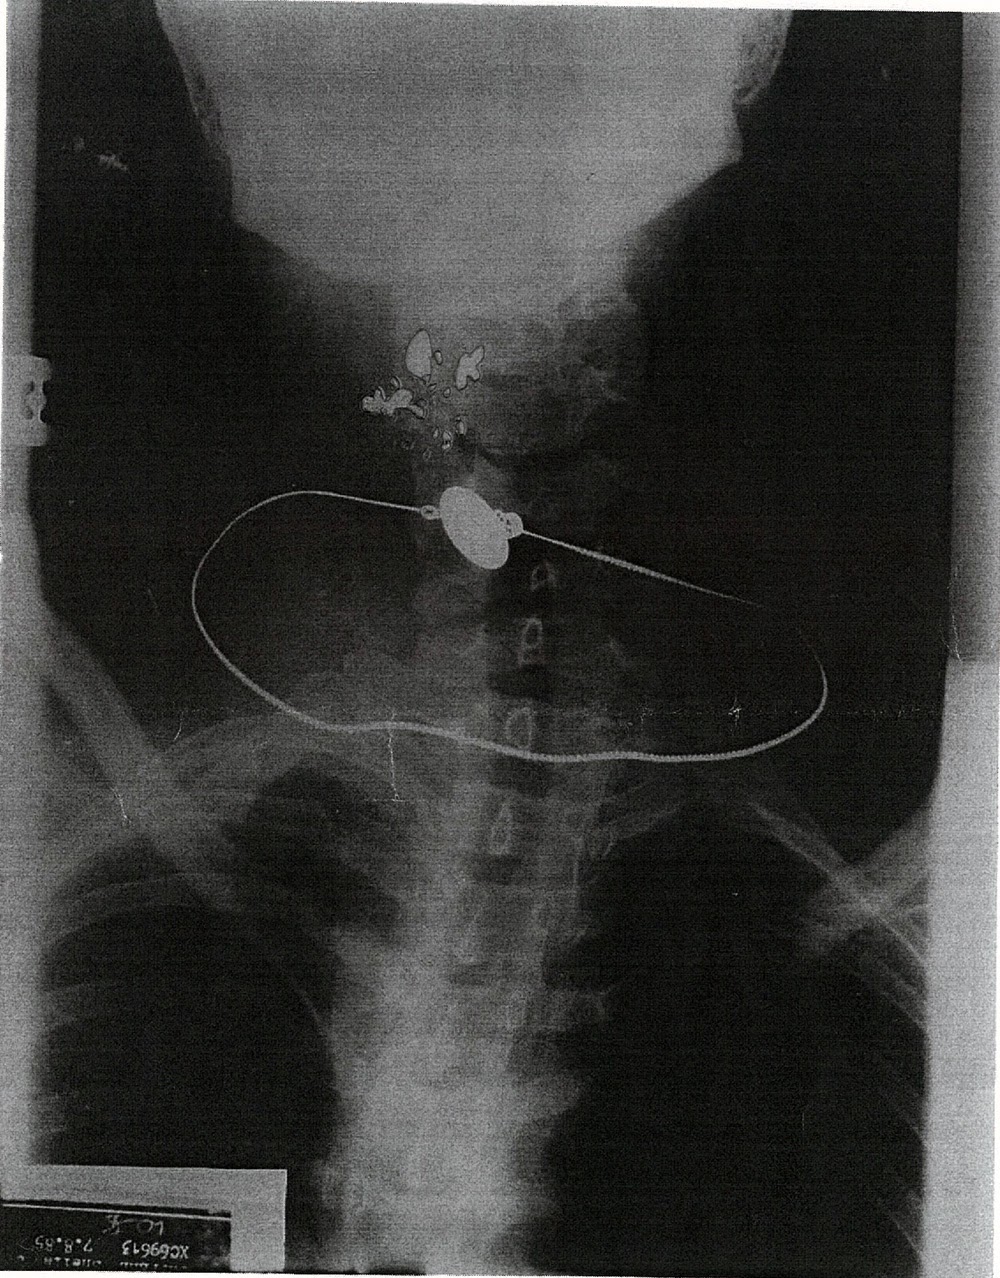

La radiografía del cadáver de Sheila